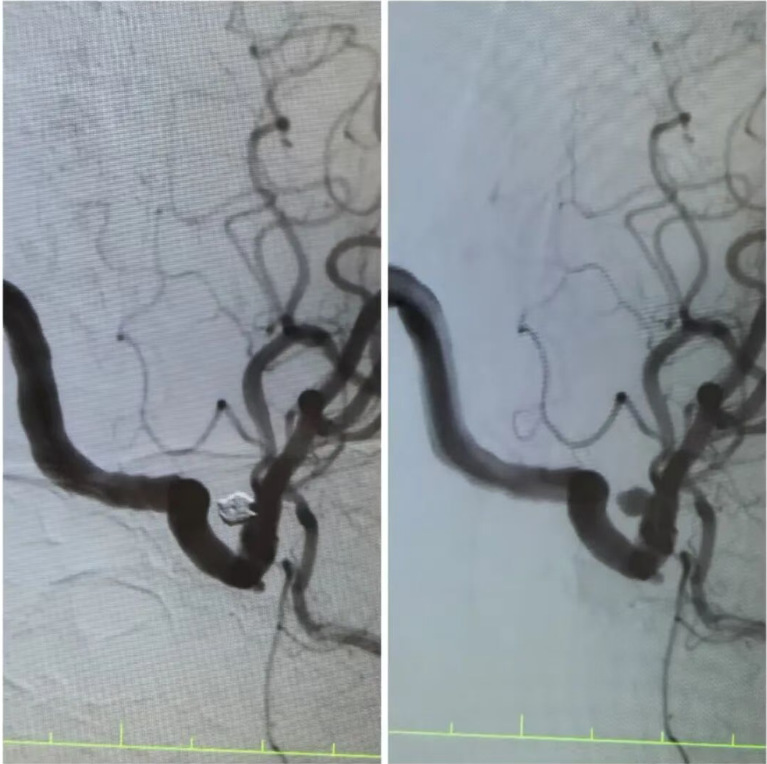

在王阿姨的造影检查上,可清晰地看到动脉瘤的形态:如同血管上悬挂的“小囊袋”,薄如蝉翼的瘤壁随时可能再次破裂。“开颅手术创伤大,老人基础疾病多,风险极高,而介入栓塞术,能通过股动脉穿刺的“钥匙孔”路径,精准封堵动脉瘤。”手术团队反复推演方案,最终选定颅内动脉瘤栓塞术——用纤细的微导管将弹簧圈送入动脉瘤腔内,像“织网”一样填充瘤腔,隔绝血流冲击,从根源上消除破裂风险。

手术台上,丁院长握着导管在血管中精准穿梭,如同在迷宫中寻找唯一的出口。当微弹簧圈依次填入动脉瘤,造影显示瘤腔被完美“封堵”,载瘤动脉血流恢复通畅,这枚困扰老人许久的“炸弹”,终于被安全拆除。术后的王阿姨头晕头痛症状消失,胸闷气短的老毛病也因身心状态改善而减轻。“感觉脑袋里的‘炸弹’没了,整个人都轻快了!”